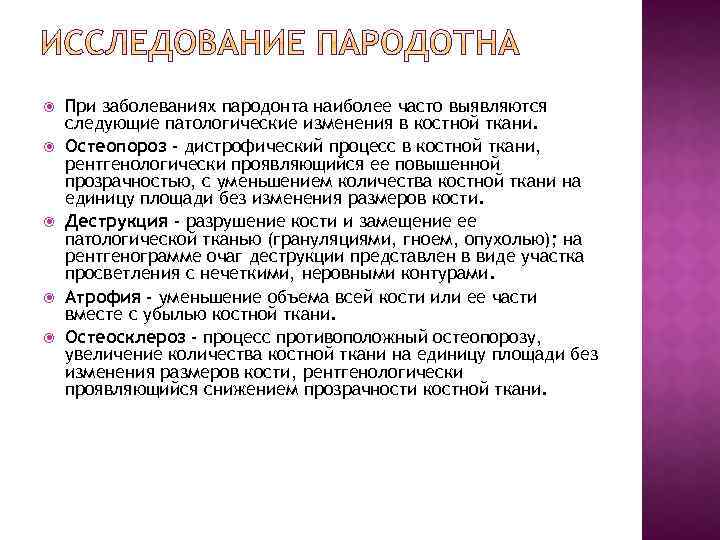

При заболеваниях пародонта наиболее часто выявляются следующие патологические изменения в костной ткани. Остеопороз - дистрофический процесс в костной ткани, рентгенологически проявляющийся ее повышенной прозрачностью, с уменьшением количества костной ткани на единицу площади без изменения размеров кости. Деструкция - разрушение кости и замещение ее патологической тканью (грануляциями, гноем, опухолью); на рентгенограмме очаг деструкции представлен в виде участка просветления с нечеткими, неровными контурами. Атрофия - уменьшение объема всей кости или ее части вместе с убылью костной ткани. Остеосклероз - процесс противоположный остеопорозу, увеличение количества костной ткани на единицу площади без изменения размеров кости, рентгенологически проявляющийся снижением прозрачности костной ткани.